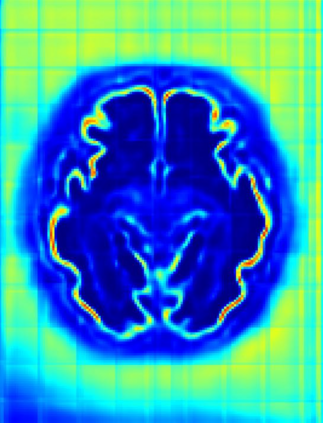

Fetal cortical plate segmentation is essential in quantitative analysis of fetal brain maturation and cortical folding. Manual segmentation of the cortical plate, or manual refinement of automatic segmentations is tedious and time-consuming. Automatic segmentation of the cortical plate, on the other hand, is challenged by the relatively low resolution of the reconstructed fetal brain MRI scans compared to the thin structure of the cortical plate, partial voluming, and the wide range of variations in the morphology of the cortical plate as the brain matures during gestation. To reduce the burden of manual refinement of segmentations, we have developed a new and powerful deep learning segmentation method. Our method exploits new deep attentive modules with mixed kernel convolutions within a fully convolutional neural network architecture that utilizes deep supervision and residual connections. We evaluated our method quantitatively based on several performance measures and expert evaluations. Results show that our method outperforms several state-of-the-art deep models for segmentation, as well as a state-of-the-art multi-atlas segmentation technique. We achieved average Dice similarity coefficient of 0.87, average Hausdorff distance of 0.96 mm, and average symmetric surface difference of 0.28 mm on reconstructed fetal brain MRI scans of fetuses scanned in the gestational age range of 16 to 39 weeks. With a computation time of less than 1 minute per fetal brain, our method can facilitate and accelerate large-scale studies on normal and altered fetal brain cortical maturation and folding.